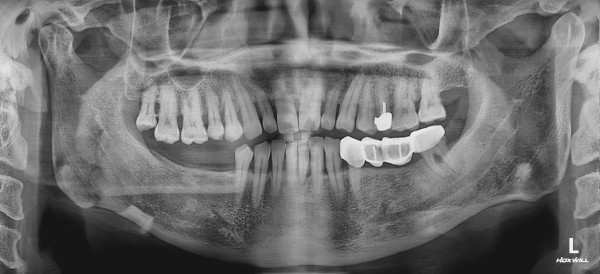

CASE 01 최고관리자 0건 25-01-06 11:58 본문 발치 후 즉시 임플란트 목록 이전글CASE 01 25.01.06 다음글CASE 01 25.01.06 댓글목록 0 댓글목록 등록된 댓글이 없습니다.